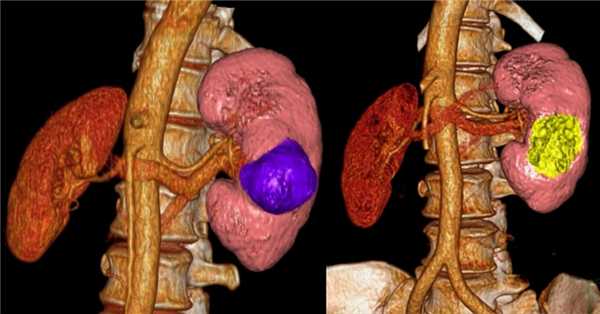

В зависимости от стадии и расположения опухоли, хирургическим методом может быть удалена только опухоль с окружающей частью почки — так называемая резекция почки, либо целая почка с опухолью — нефрэктомия. Надпочечниковая железа и жировая ткань вокруг почки также может быть удалена вместе с почкой, если возникнет необходимость.

Резекция почки

В ходе данной процедуры, хирург удаляет только ту часть почки, которая содержит опухоль, оставляя оставшуюся ткань почки неповрежденной. В настоящий момент это предпочтительный метод лечения для пациентов с ранней стадией рака почки. Часто резекции вполне достаточно для удаления одиночных небольших опухолей до 4 см в диаметре.

Также этот метод может применяться у пациентов с бОльшими образованиями, до 7 см. Специалистами НИИ онкологии им. Н.Н. Петрова успешно выполнялись вмешательства на опухолях размерами 10 и более см, однако такие операции возможны только в отдельных случаях, с учетом анатомии опухоли.

Современные исследования показали, что отдаленные результаты у пациентов, перенесших резекцию почки, почти такие же, как у пациентов, у которых почка была удалена. Однако несомненным плюсом остается сохранение большей части почечной функции.

После резекции почки, для определения функционального состояния пациента в НИИ онкологии проводится перфузия почки.